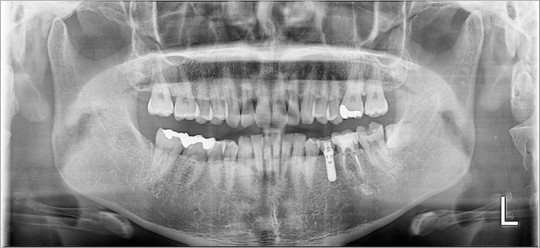

①パノラマ

パノラマは歯列矯正以外の治療でも必須のレントゲンです

事前に撮影することで

虫歯や歯周病、根の状態、顎関節、親知らずや上顎洞(副鼻腔)

安全に治療できるか、事前にやっておくことはないか

をチェックしています

矯正歯科にかかわらず、どこの医院でも撮影している

とても重要なレントゲンです